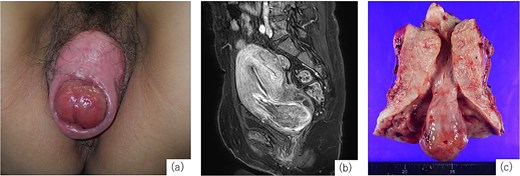

A 52-year-old woman, gravida 4, para 3, with regular menstrual cycles presented with a 9-year history of vaginal discomfort and recent abnormal menstrual bleeding. She had a history of mild POP, but no prior treatment. Although the discomfort had not improved, she did not visit a gynecologist. She visited a gynecologist with complaints of increased menstrual bleeding and a drooping sensation and was diagnosed with fibroid expulsion and POP, and 2 months later, referred to our department. The gynecological assessment revealed fibroid expulsion with complete uterine prolapse, cystocele, rectocele and a prolapsed mass visible in the external cervical os (Fig. 1a). Contrast-enhanced magnetic resonance imaging (MRI) identified a pedunculated submucosal fibroid (69 × 42 × 50 mm) originating from the anterior uterine wall and extending through the cervical canal (Fig. 1b). Her blood tests showed anemia (hemoglobin [Hb]: 9.2 g/dL); therefore, preoperative management with relugolix (40 mg/day), a GnRH antagonist, was planned. On day 33 of treatment, the patient experienced heavy, uncontrolled vaginal bleeding and was admitted for emergency surgery. Given the significant size of the uterus and the fibroids, laparoscopic surgery and vaginal total hysterectomy (VTH) are deemed infeasible. Therefore, an abdominal approach was used. Abdominal total hysterectomy (ATH), bilateral salpingectomy, colporrhaphy, and perineoplasty. Surgery was performed with the patient in the lithotomy position. The uterus was markedly enlarged to the size of a large fist, and the uterovesical fold of the peritoneum was significantly descended owing to complete uterine prolapse, complicating its dissection and elevation. The uterine isthmus widened because of fibroid expulsion, obscuring the localization of the uterine vaginal junction. After treating the round, utero-ovarian, and cardinal ligaments, a vertical incision was made on the anterior vaginal wall to identify the distal margins of the vaginal vault. Colpotomy was then performed to excise the uterus. Subsequently, the procedure was transitioned to a vaginal approach to repair the bladder and rectal prolapse. The vaginal wall closure was completed after colporrhaphy. The operative time was 3 h and 57 min, with an estimated blood loss of 470 mL. The resected specimen revealed a pedunculated mass originating from the posterior uterine wall (Fig. 1c). On the fifth postoperative day, the indwelling urinary catheter was removed, and normal urination was confirmed. The patient was discharged on the 13th postoperative day. At the 1-month postoperative follow-up, the patient exhibited no abnormalities and was deemed to have recovered, concluding her treatment.

Examination findings. (a) Complete uterine prolapse with a mass protruding through the external cervical os. (b) Contrast-enhanced magnetic resonance imaging (T1-weighted) shows a submucosal fibroid originating from the anterior uterine wall descending through the cervical canal. (c) Resected specimen shows uterine cross-section showing a 3-cm stalked fibroid extending through the cervical canal.

Fibroid expulsion occurs when a submucosal fibroid protrudes through the cervical canal, often becoming symptomatic, and is a common cause of AUB [1]. POP is the descent of the pelvic organs due to weakened support structures, influenced by genetic predisposition, neuropathy, myopathy, childbirth, and contributing factors such as obesity, smoking, pulmonary disease, and constipation [5], and is most prevalent among postmenopausal women [5]. The coexistence of fibroid expulsion and POP is rare, and only a few surgical case reports under different conditions have been published. Necrotic pedunculated prolapsed submucosal fibroids cases complicated by complete utero-vaginal prolapse treated with VTH are reported [6, 7]. Necrosis may occur due to compromised blood flow through the stalk; however, in our case, the stalk was 3 cm thick, which likely preserved the blood supply.